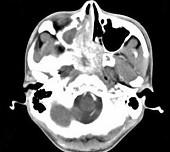

问题 男,20岁,头痛、鼻塞、鼻出血,CT如图所示,最可能诊断为()

选项 A.鼻咽癌 B.巨大的鼻息肉 C.鼻咽纤维血管瘤 D.鼻咽神经纤维瘤 E.鼻咽腺样体增生

答案 C